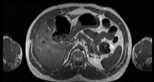

Visible Human male: Sectio transversalis 1559

CT

NMR

Pd                          / T2 \                         T1